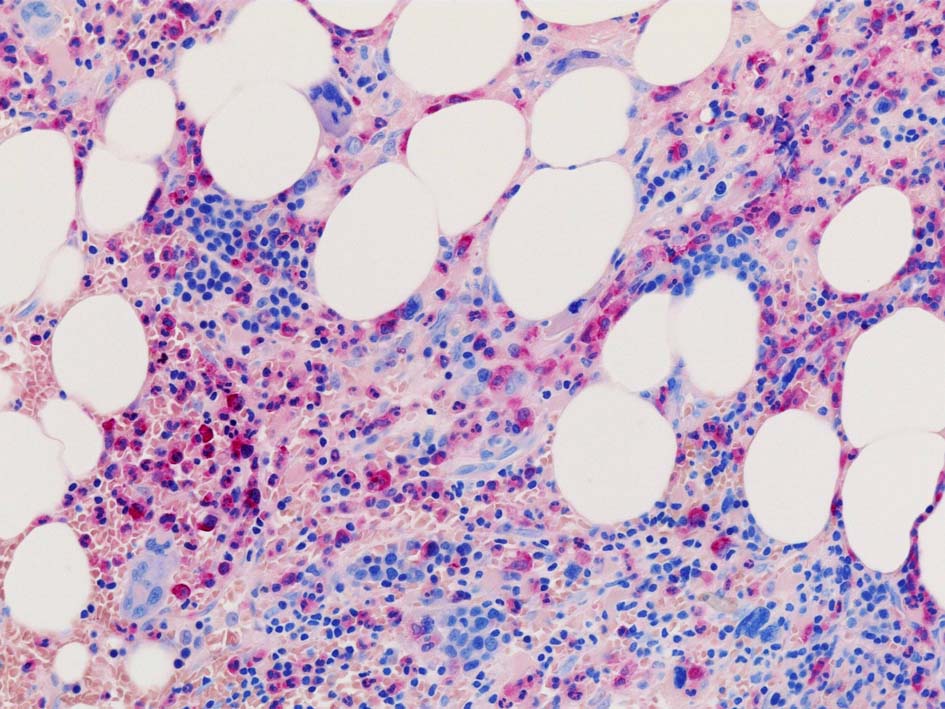

塗銀染色

CD42b染色

黒染する弾性線維の増生のほか, 赤く染まる膠原線維の増生が確認される. MF-2 fibrosis. 鍍銀染色の核染色をすると膠原線維の赤染がわからなくなるので行わない.